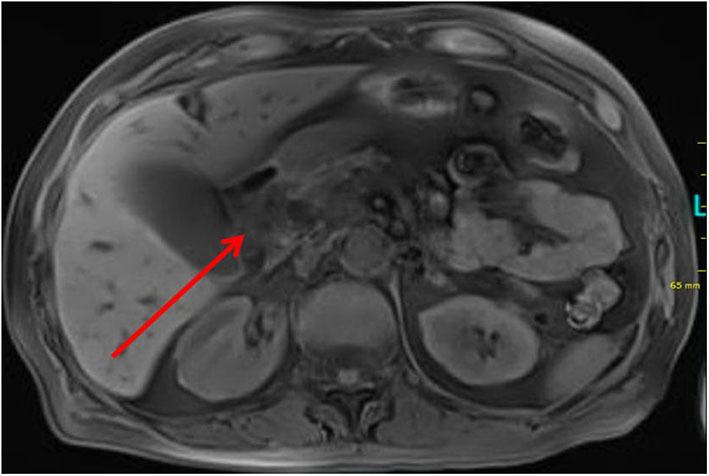

Bühler's anastomosis (or Bühler's arcade) is an embryonic relic and represents an arterio-arterial connection between the superior mesenteric artery and the celiac trunk. It can be found as a variety in 1-2% of patients. We present a case of a patient with metatastatic squamous cell carcinoma of the lung. The patient was in stable disease for 4 years under palliative therapy (most recently second-line therapy with Nevolumab). In 2019, a locally advanced adenocarcinoma of the papilla vateri was diagnosed, additionally. The patient also underwent right hemicolectomy and patch plasty of the celiac trunk and superior mesenteric artery due to colonic ischemia and arteriosclerotic disease with 50-70% stenosis of the superior mesenteric artery several years ago. Due to a complex vascular prehistory, the standardized preoperative imaging was supplemented by two independent vascular reconstructions (a CT angiogram and a reconstruction based on the CT) for the planning of a pylorus-preserving pancreatic head resection and reconstruction according to Traverso-Longmire. In addition, a 3D print was produced. Both, the reconstruction based on the CT scan and the 3D print were created for off-label use as a part of a research project (VIVATOP: Versatile Immersive Virtual and Augmented Tangible OP). In the standardized CT scan and in the clinical CT-angiography, there were no obvious surgically relevant anatomical variations. A Bühler anastomosis was detected in a digital, virtual and interactive 3D-reconstruction. In addition, in the 3D print of the abdominal site the anastomosis was seen as well. Intraoperatively, the presence of Bühler's anastomosis was confirmed. This information had a significant impact on the intraoperative approach. Retrospectively, the vessel variant could be surmised in the axial projection of the CT scan, if one knew what to look for. For the conduction of a safe surgical procedure, it is imperative that rare anatomical variations are known preoperatively. Increasing digitalization in surgical and perioperative preparation holds great potential for better planning and improved patient safety. Research and cooperation projects such as the VIVATOP project are instrumental for the development of new visualization techniques, which are able to enhance the understanding of complex anatomical relations.

比勒吻合术(或比勒血管弓)是一种胚胎遗迹,代表肠系膜上动脉与腹腔干之间的动脉-动脉连接。在1%-2%的患者中可发现其存在多种类型。我们报告一例肺转移性鳞状细胞癌患者。该患者在姑息治疗(最近为纳武单抗二线治疗)下病情稳定4年。此外,2019年诊断出壶腹周围局部晚期腺癌。几年前,该患者还因结肠缺血和动脉硬化性疾病,肠系膜上动脉狭窄50%-70%,接受了右半结肠切除术以及腹腔干和肠系膜上动脉补片成形术。由于血管病史复杂,在根据特拉弗索-朗迈尔法进行保留幽门的胰头切除和重建手术规划时,标准化的术前影像通过两次独立的血管重建(一次CT血管造影和一次基于CT的重建)进行补充。此外,还制作了一个3D打印模型。基于CT扫描的重建和3D打印模型均作为一个研究项目(VIVATOP:多功能沉浸式虚拟和增强实体手术)的一部分用于非标签用途。在标准化CT扫描和临床CT血管造影中,未发现明显的与手术相关的解剖变异。在数字化、虚拟和交互式3D重建中检测到了比勒吻合术。此外,在腹部区域的3D打印模型中也看到了该吻合术。术中证实了比勒吻合术的存在。这一信息对术中操作方法产生了重大影响。回顾性分析,如果知道要寻找什么,在CT扫描的轴向投影中可以推测出血管变异。为了进行安全的外科手术,术前了解罕见的解剖变异至关重要。手术和围手术期准备中日益增加的数字化对于更好的手术规划和提高患者安全性具有巨大潜力。像VIVATOP项目这样的研究与合作项目有助于开发新的可视化技术,能够增强对复杂解剖关系的理解。